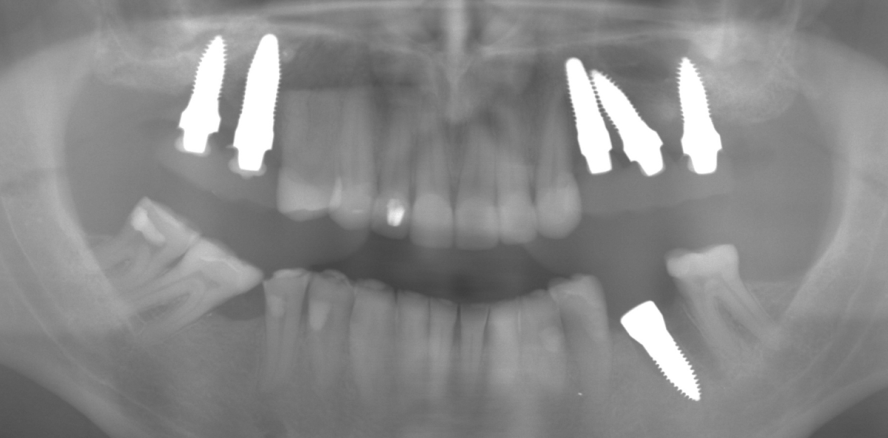

Zum Einsatz kamen die SDS-Implantate im Root Design (SDS RD ATZ), die auch bis zu einem Durchmesser von 5,4 mm verfügbar sind. Diese wurden alle mit demselben Drehmoment von ca. 35 Ncm primärstabil inseriert. Lediglich in den Bereichen 15 und 24 kam jeweils eine Haltnaht (PTFE) zum Einsatz. Die SDS-Zirkonimplantate wurden mit Rotringdiamanten präpariert und dabei in der Achsabweichung korrigiert. Mittels einer Tiefziehfolie (Formteil) wurden die Provisorien aus Protemp® 4 (3M ESPE) chairside gefertigt und mit Durelon® (Carboxylatzement der Firma 3M ESPE) eingesetzt. Die provisorische Versorgung war beidseitig außer Funktion eingeschliffen worden, um jegliche Überbelastung zu vermeiden. Der Patient wurde darauf hingewiesen, die Provisorien kaum zu belasten und nur weiche Kost zu sich zu nehmen. Trotz langer Operationsdauer hatte der Patient am Folgetag keine Schmerzen und auch keine Schwellungen.

Nach drei Monaten Einheilzeit wurden die Implantate freigelegt und mit Rotringdiamanten am Beispiel eines natürlichen Zahnes feinpräpariert. Anschließend erfolgte ein Abdruck mit Impregum™ (3M ESPE). Die provisorische Versorgung wurde erneut aus Protemp™ 4 chairside gefertigt und mit Durelon® eingesetzt.

Vier Wochen später wurden die definitiven Zirkonbrücken ebenfalls mit einem Glasionomerzement (Fuji PLUS™, GC) definitiv eingesetzt. Bei der abschließenden Okklusions- und Artikulationskontrolle ist darauf zu achten, den Zahnersatz in leichter Infraokklusion (Shimstock-Folie ohne Widerstand) und ohne jegliche Artikulationskontakte einzuschleifen.